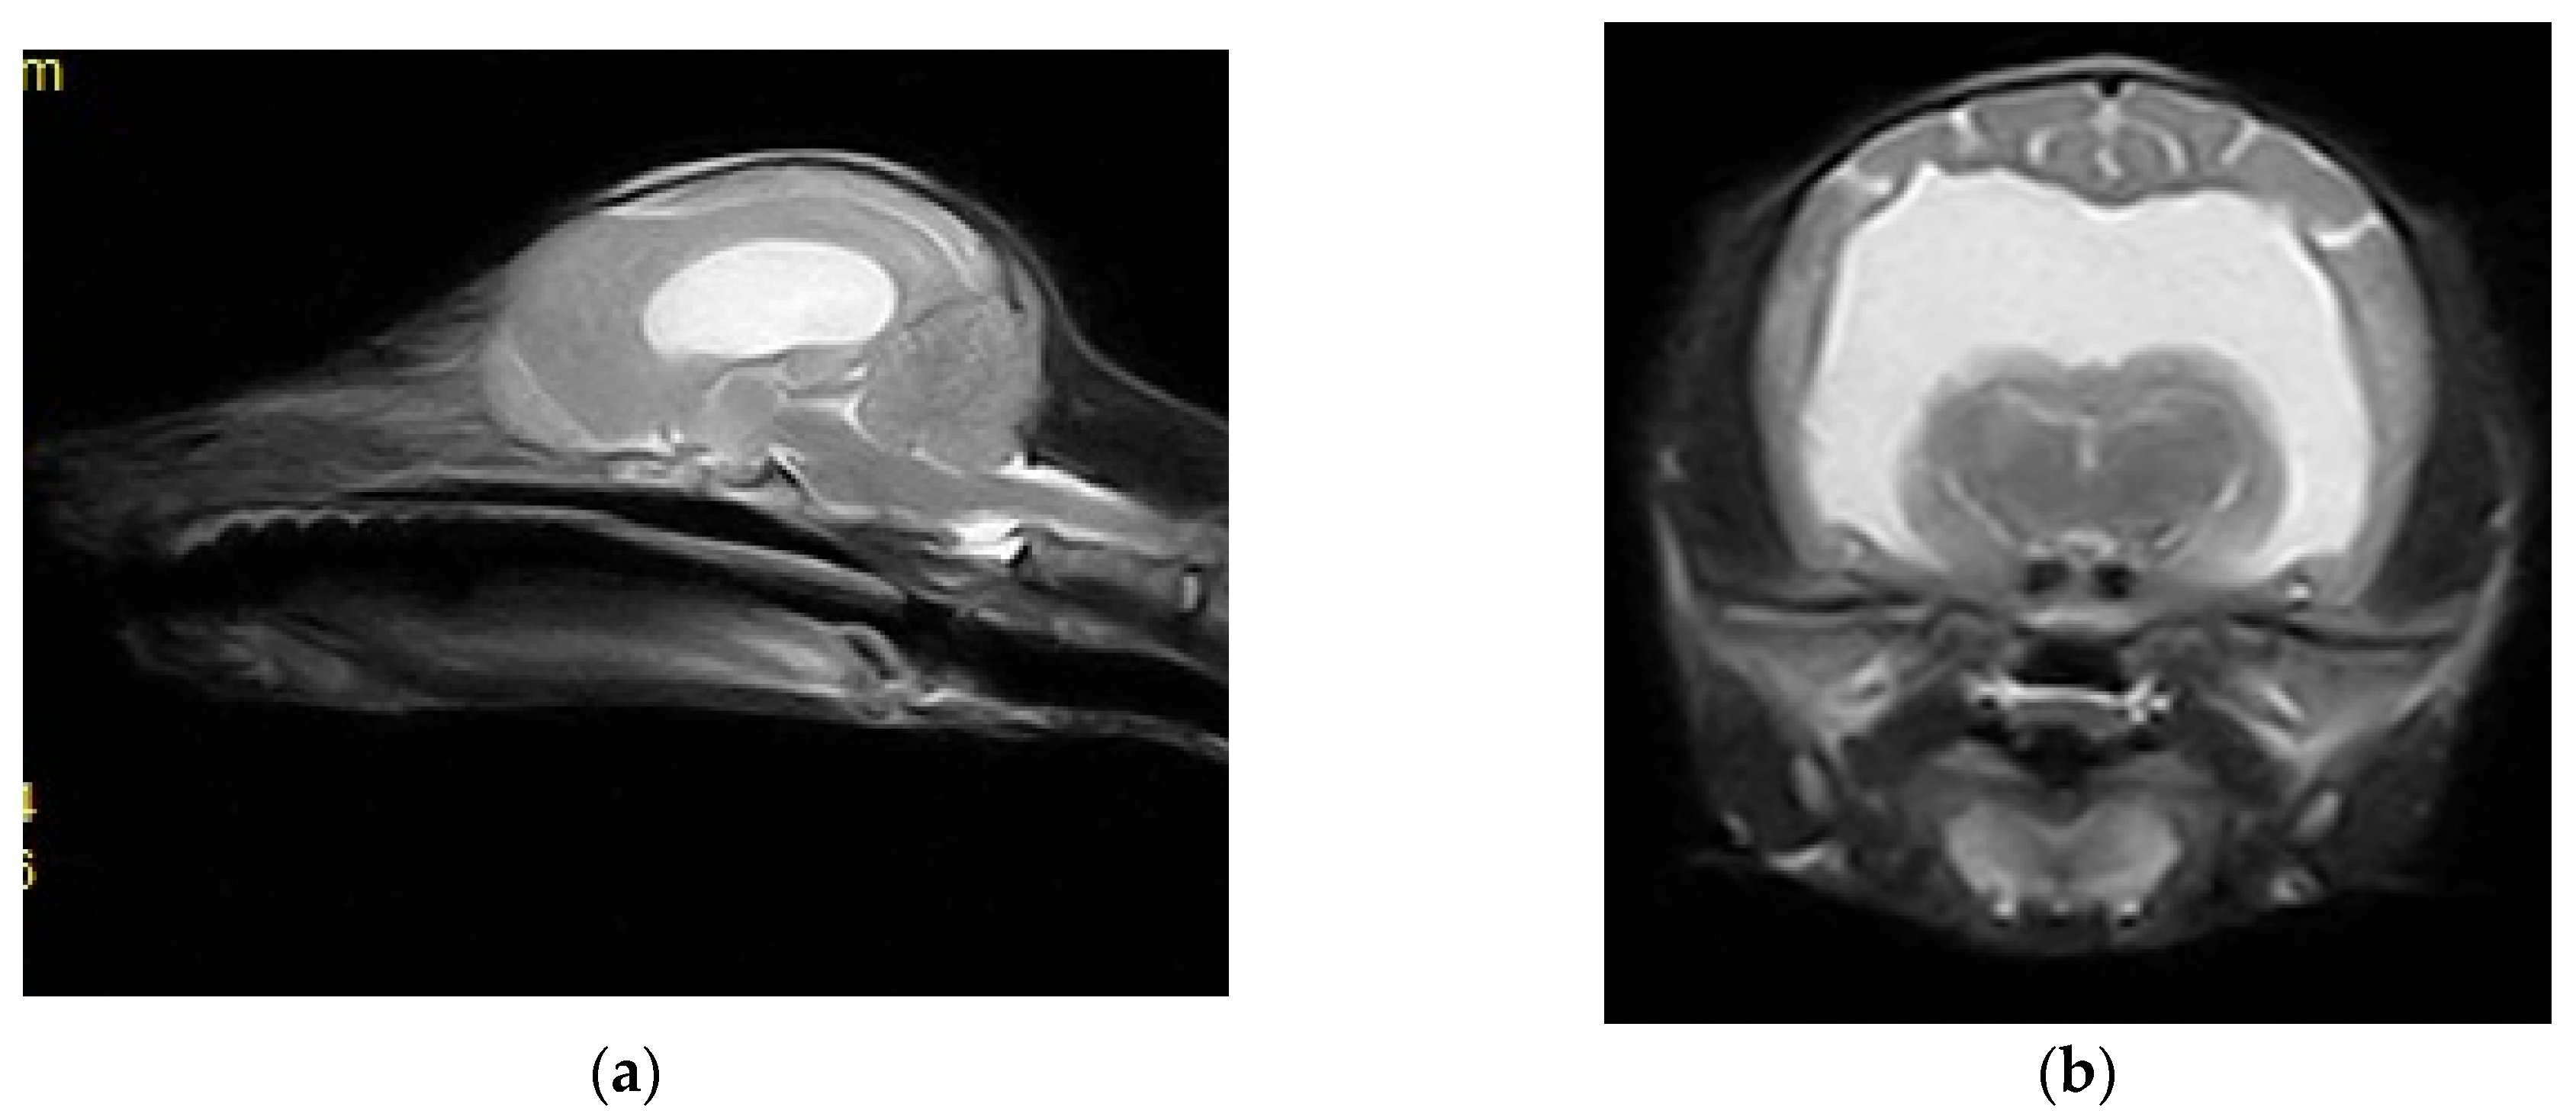

2. Case Description

- Raposo, M.; Añor, S.; Verdés, J.; Soler, V.; Martorell, J. Diagnosis and Treatment of Congenital Hydrocephalus in a Red Fox (Vulpes vulpes) with Seizures. Vet. Rec. Case Rep. 2022, 10, e310. [Google Scholar] [CrossRef]